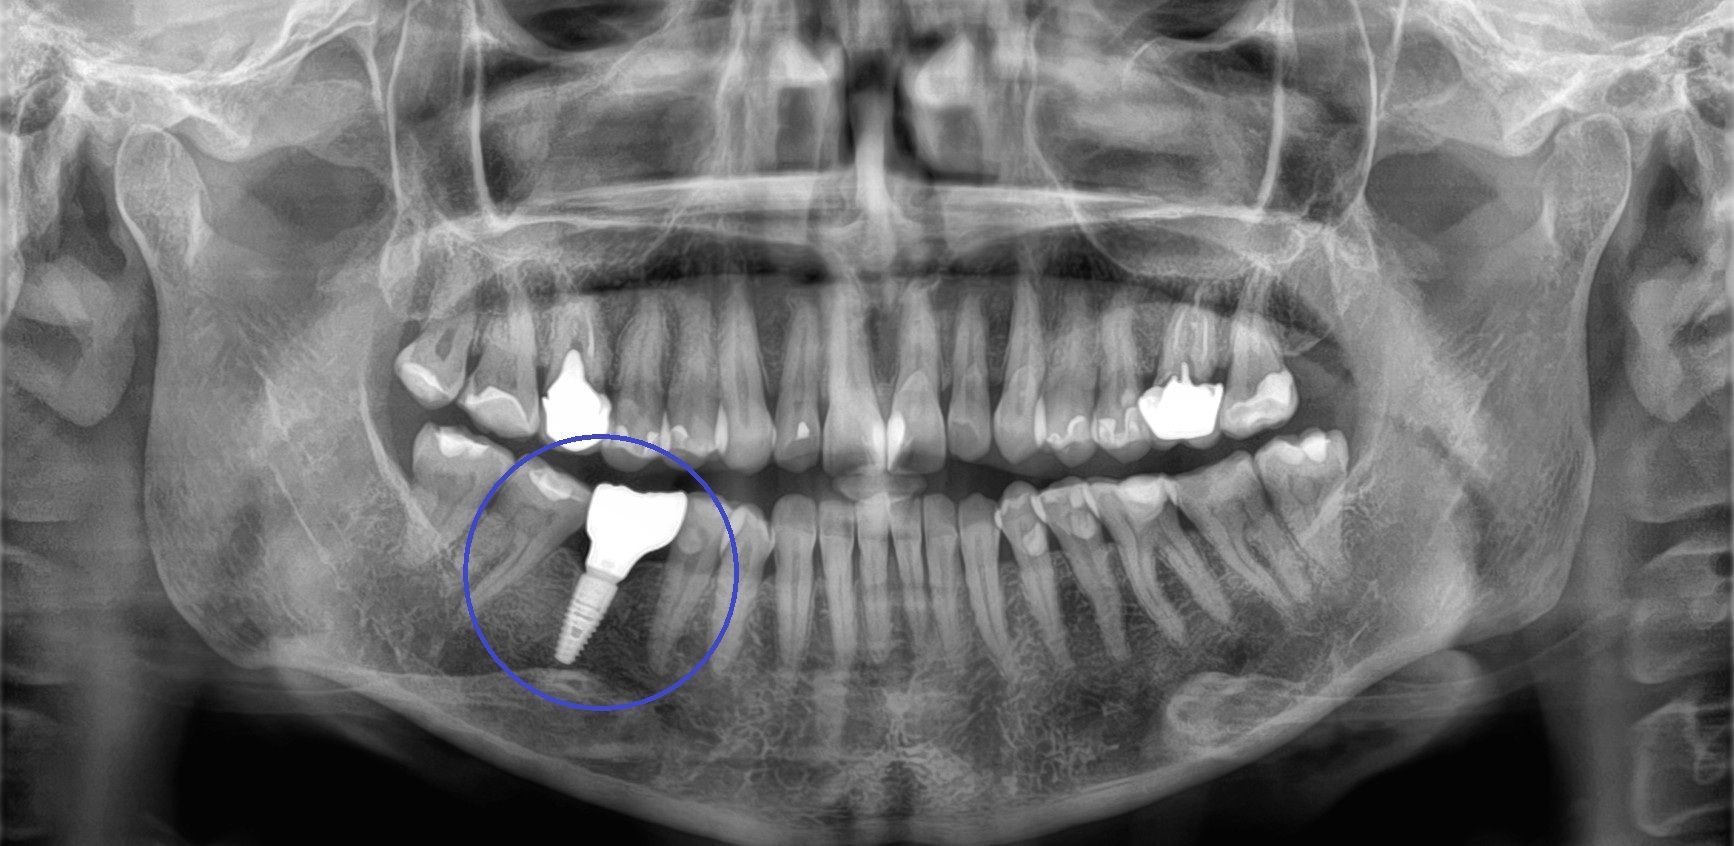

Bei brilliant smiles in Wiener Neudorf planen wir Implantate mit modernster 3D-DVT-Röntgentechnik und setzen sie präzise durch unseren erfahrenen Chirurgen.

- Künstliche Zahnwurzeln aus Titan oder Keramik

- Dauerhaft im Kiefer verankert – vergleichbar mit natürlichen Zahnwurzeln

- Grundlage für Kronen, Brücken oder Prothesen

- Biokompatibel und besonders langlebig

- Einzelimplantat mit Implantatkrone – ersetzt einen einzelnen Zahn